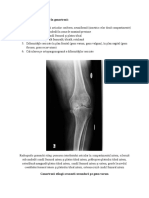

Dolicosigmoid asociat cu distensie colonica

PARACLINIC – Rx abdominala simpla/ clisma baritata

Volvulus de Cec